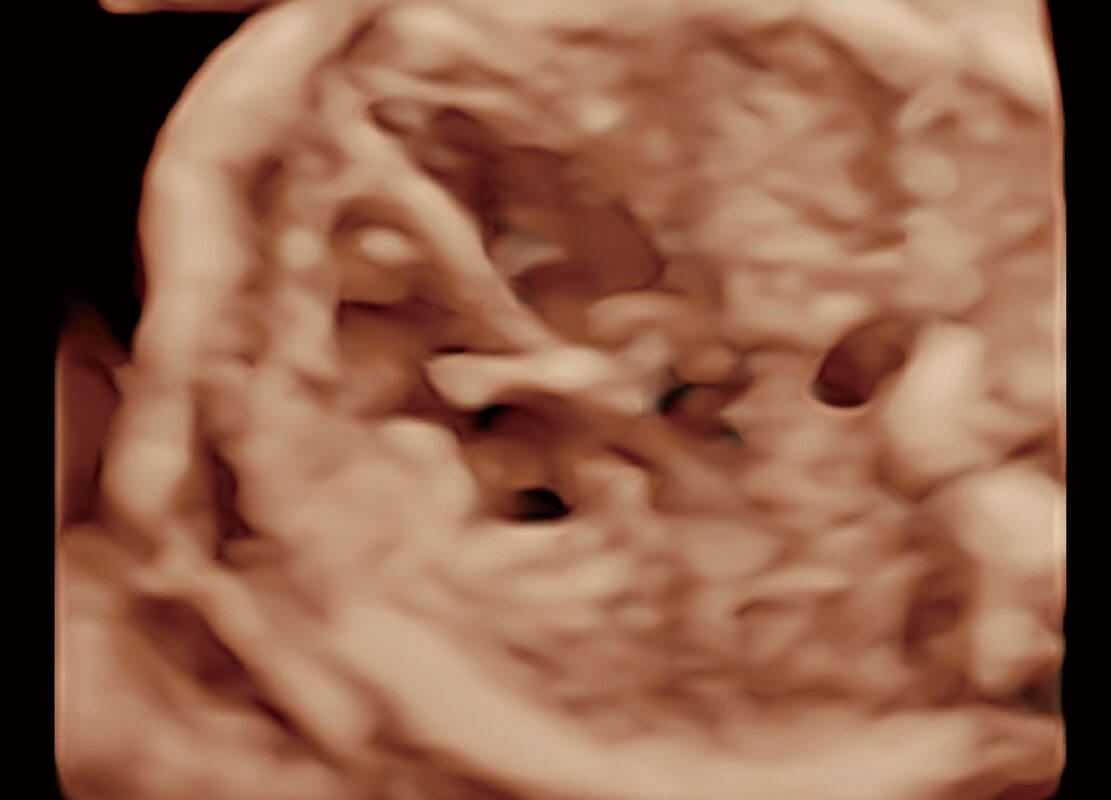

胎心筛查

P60搭载一系列胎儿心脏成像技术,实现更精细的胎儿心脏评估。

• 四腔切面

• 四腔心血流

• 右室双出口

• 胎心容积成像